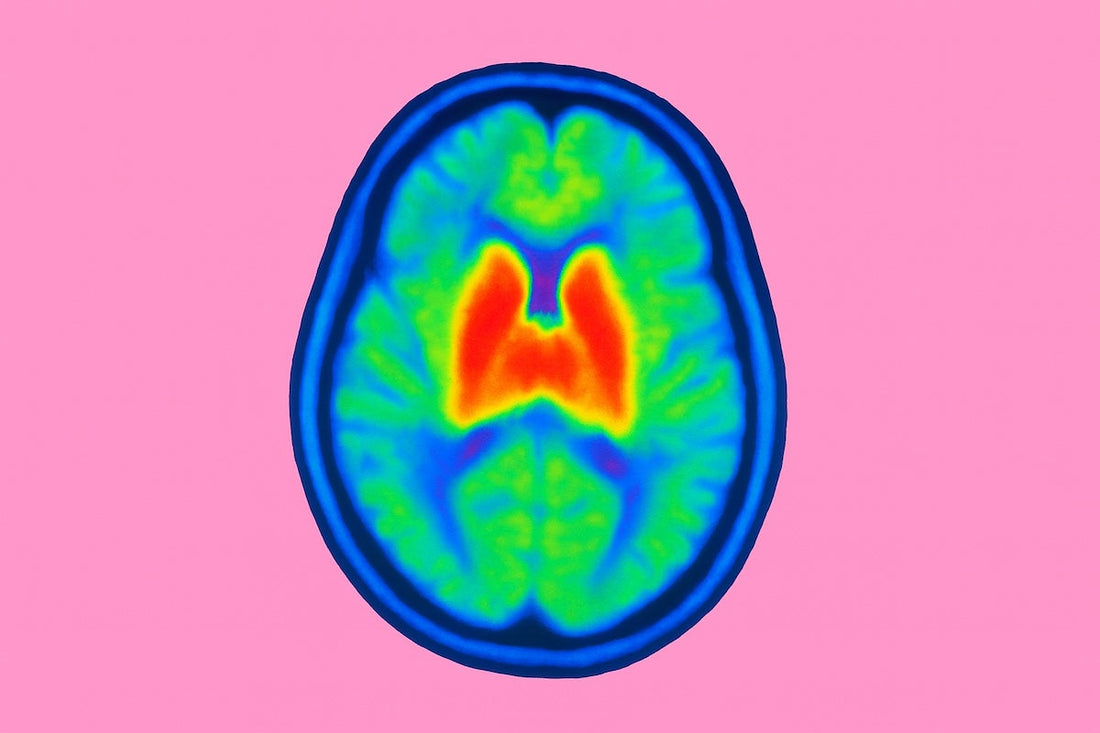

- Advanced imaging: PET scans that detect microglial activation